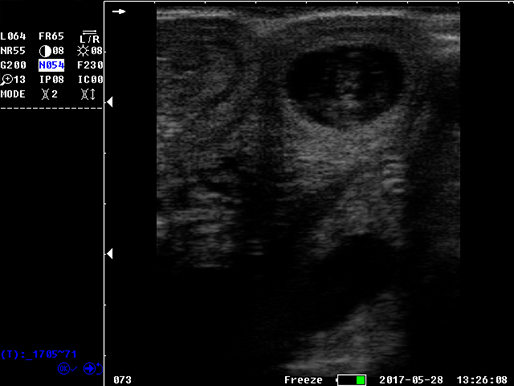

B模式 猪孕检

猪孕检

猪孕检

猪孕检